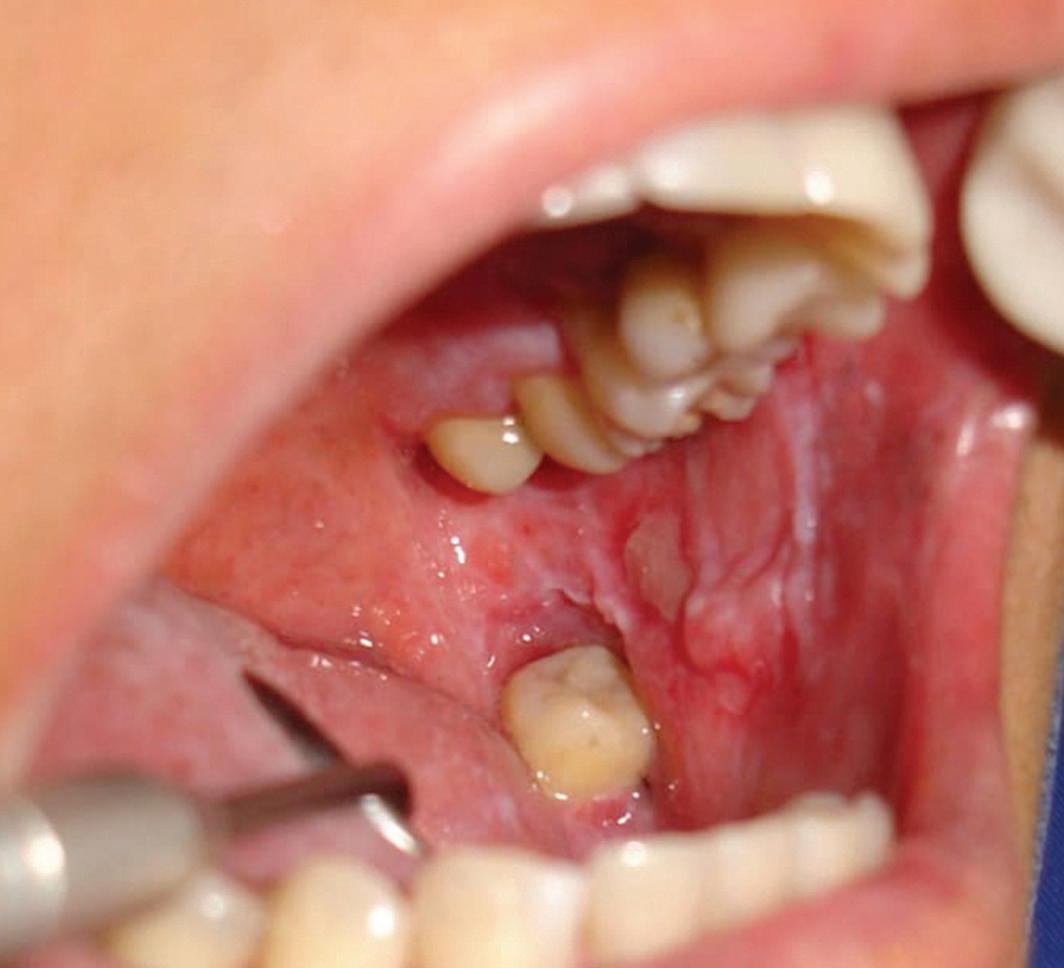

59 Oral Medicine, Oral Diagnosis, Oral Pathology

Malignant transformation of oral lichen planus after 6 years: a case report